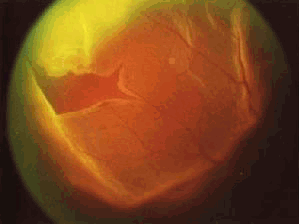

视网膜脱离